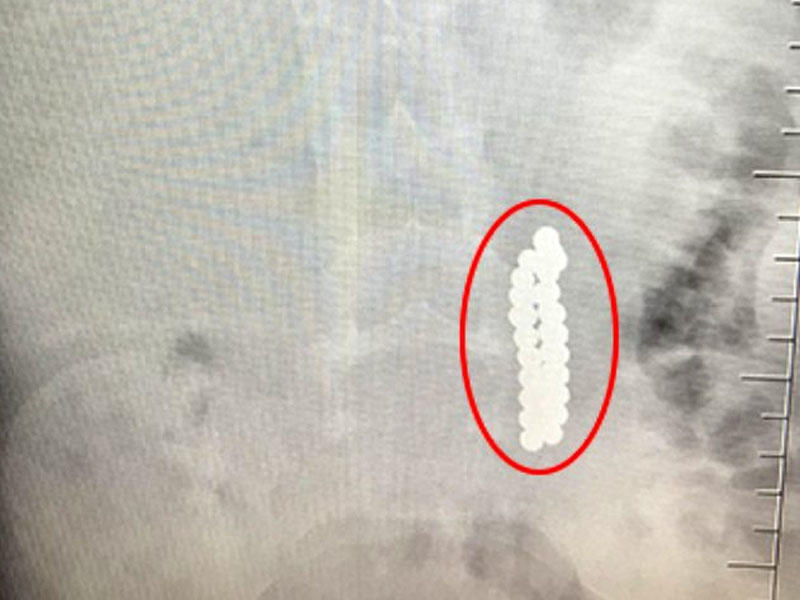

Məlum olub ki, uşağın mədəsində neodymium adlanan "stres topu" kimi tanınan 42 maqnit muncuq var. Qusma və qarın ağrısı şikayətiylə xəstəxanaya gətirilən uşağın deşilən bağırsağından maqnitlər çıxarılıb.

Bu da həmin kadrlar: